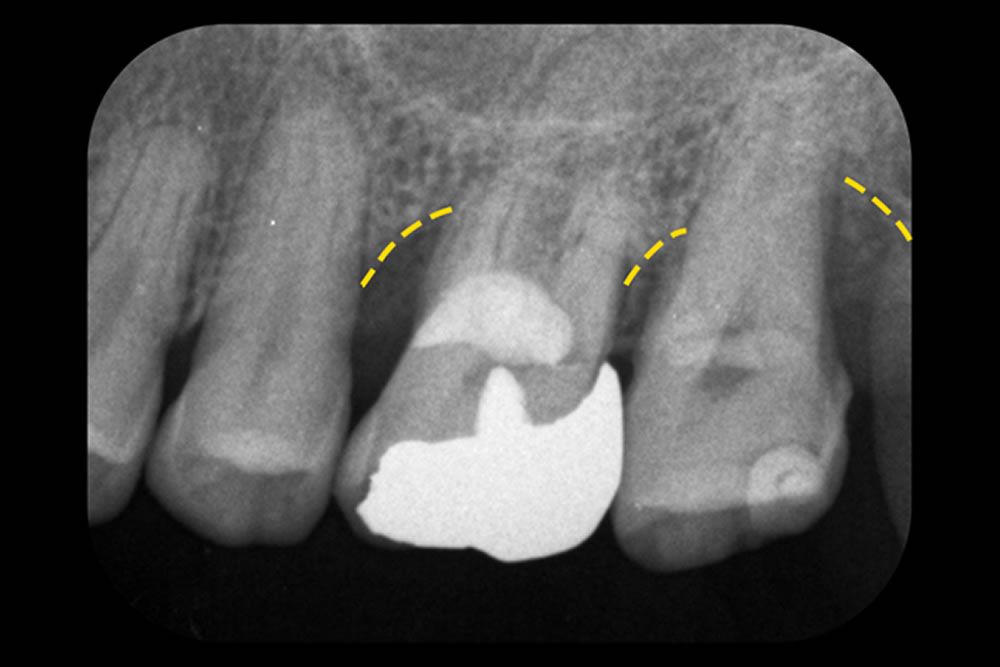

MIST・レーザー等で重度歯周病の症状を改善した症例 治療前 治療後 こちらの患者さまは、左上の奥歯2本(第一・第二大臼歯)に進行した歯周病があり、それぞれに「垂直性骨欠損」が見られ、分岐部にも炎症が及んでいました。非常 […]